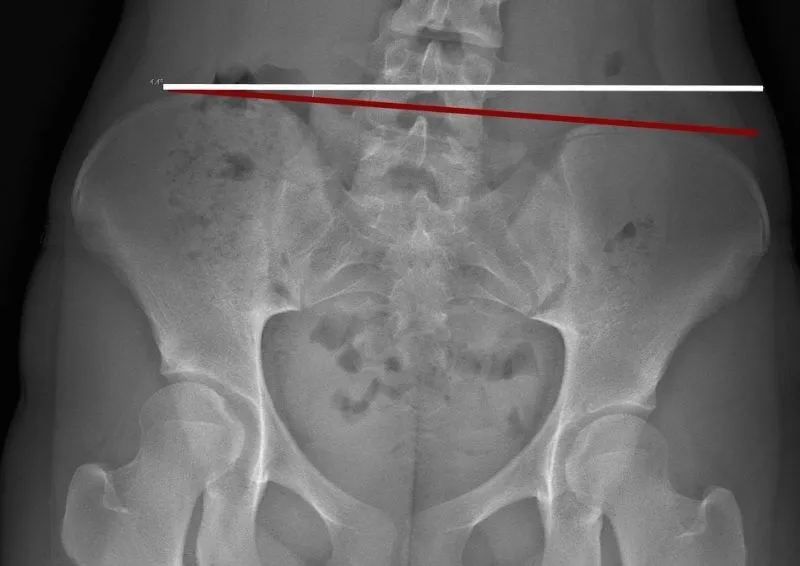

• Perform a detailed postural and spinal assessment